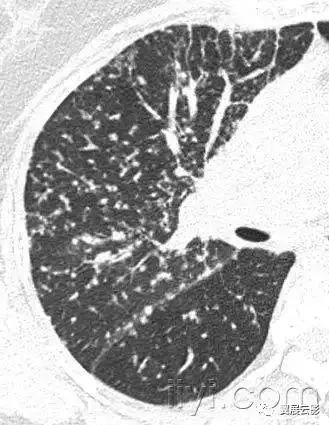

三十九、马赛克征

CT:本征象表现为不同的密度成片状镶嵌,可为间质性病变、闭塞性小气道病变(图)或者血管阻塞性疾病。马赛克征比马赛克样少血或者低灌注具有更强的诊断含义。由于支气管或细支气管阻塞导致的空气滞留可以导致局部的密度减低,在呼气相CT上表现更加明显。

该征象也可以见于间质性肺部疾病,特征是磨玻璃影,此时高密度代表间质性病变,低密度代表正常的肺。